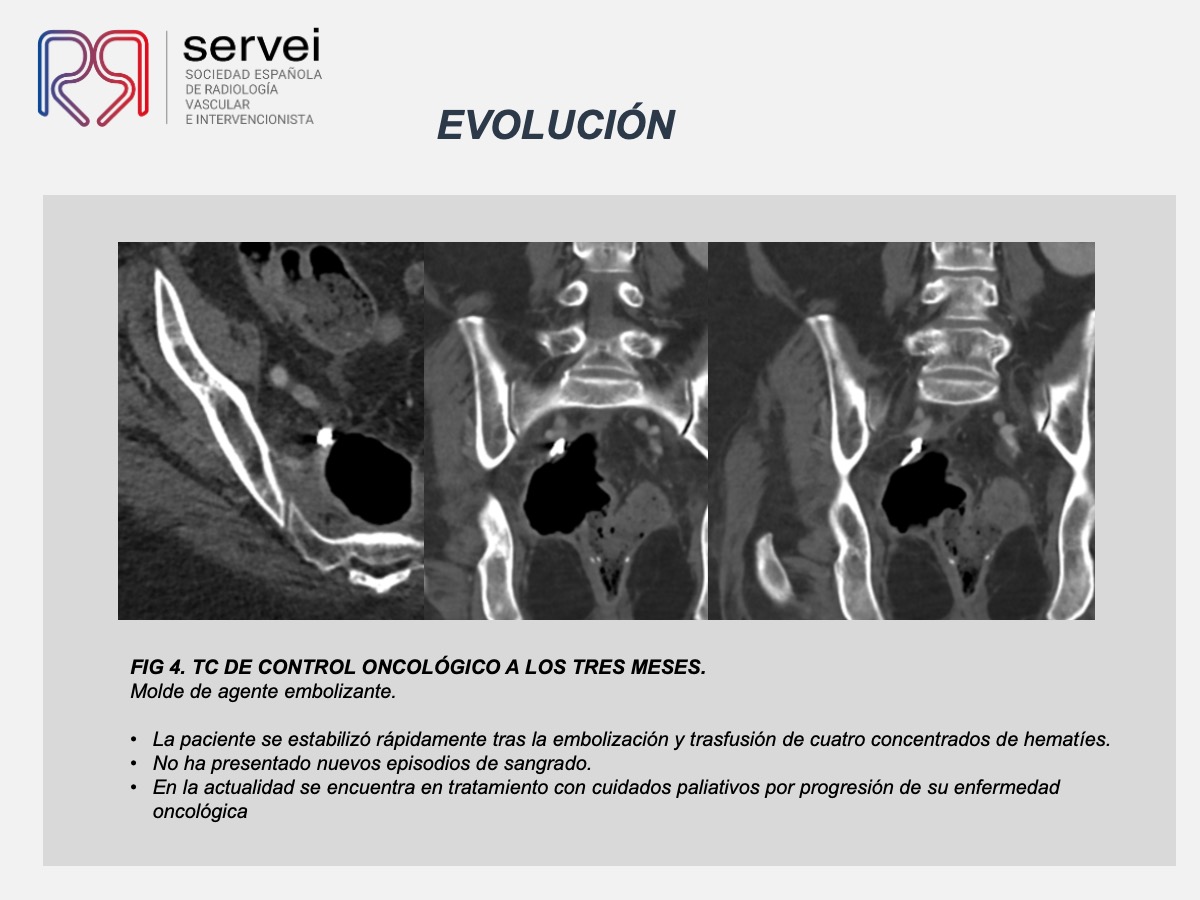

- Pseudoaneurisma arteria obturatriz-rectorragia 01

- Pseudoaneurisma arteria obturatriz-rectorragia 02

- Pseudoaneurisma arteria obturatriz-rectorragia 03

- Pseudoaneurisma arteria obturatriz-rectorragia 04

- Pseudoaneurisma arteria obturatriz-rectorragia 05

- Pseudoaneurisma arteria obturatriz-rectorragia 06

- Pseudoaneurisma arteria obturatriz-rectorragia 07

- Pseudoaneurisma arteria obturatriz-rectorragia 08

- Pseudoaneurisma arteria obturatriz-rectorragia 09